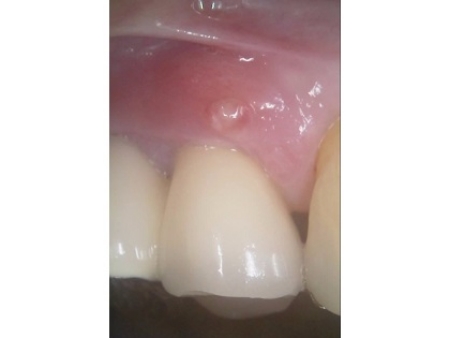

しかし、土台となっている手前の歯(第2小臼歯)は歯根が割れており、同じく土台となっている奥の歯(第2大臼歯)は歯根の先に膿の袋ができる「根尖病巣(こんせんびょうそう)」が認められます。

さらに、ブリッジ部位の歯茎は腫れ、痛みもあるとのことでした。